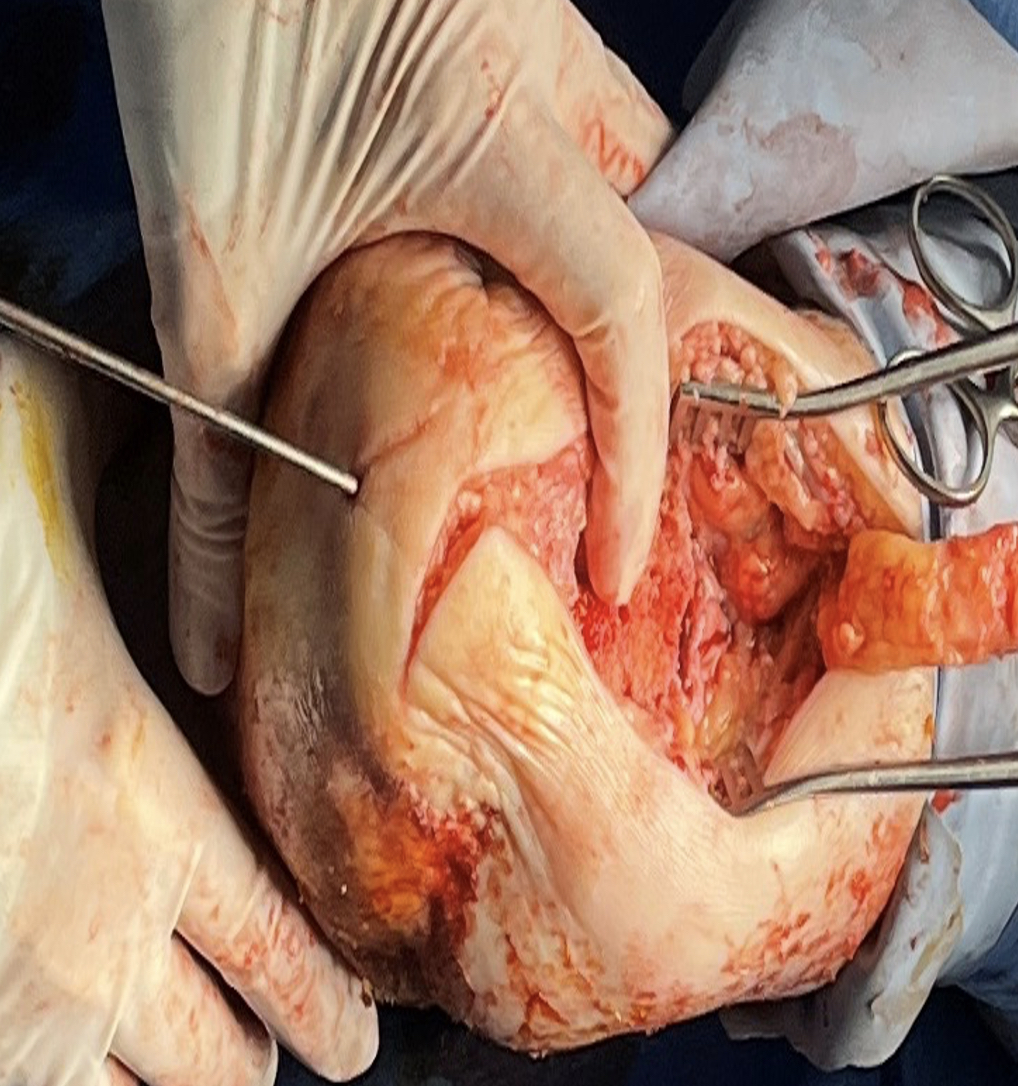

Again, misfortune occurred 10 days postoperatively with signs of wound dehiscence and necrosis, including full-thickness loss of dermal tissue extending well beyond the original incision. Also, the positioning screw had lost its fixation (see sixth photo to left). We took the patient back to the operating room, debrided the skin edges, and discovered infection and necrosis of the Achilles tendon. We removed the positioning screw and posterior locking plate and screws due to their involvement. The graft underwent debridement but overall appeared unaffected. Deep bone cultures and bone biopsy also took place.